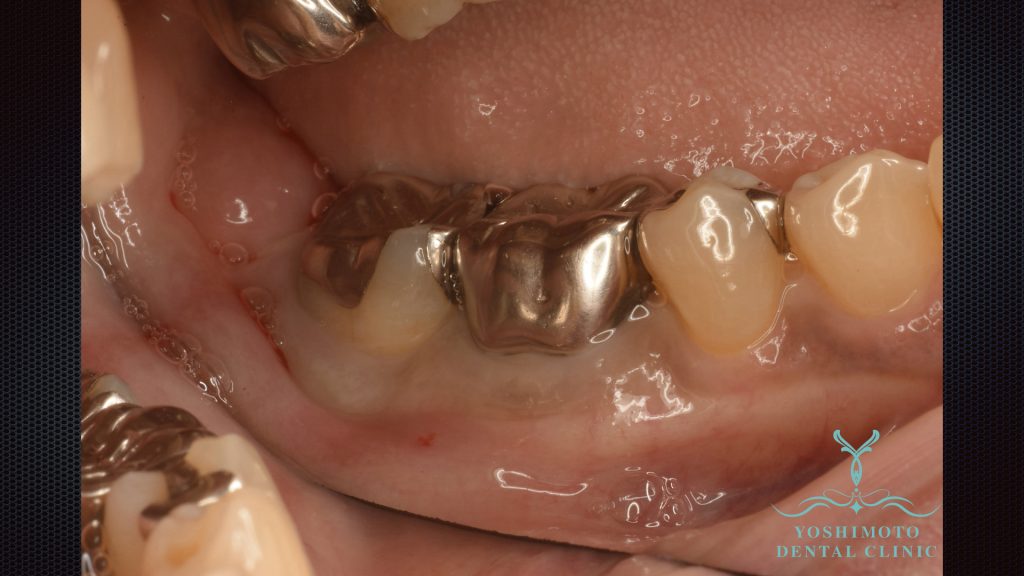

右下奥歯が定期的に腫れることが気になるため来院されました。

一見すると問題ないと思われますが、実は歯周病により歯槽骨の崩壊が進んでいました。

⇧歯周外科手術時の写真です。